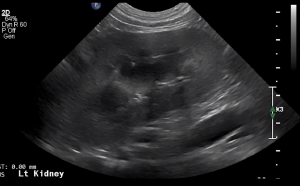

SIMON Ultrasound Database

This ultrasound database is a free resource for students and doctors!

Our collection includes videos of dogs, cats, horses, cows, humans, and many other species!

–Canine and Feline abdominal ultrasound videos were generously provided by the Cummings School of Veterinary Medicine at Tufts University.